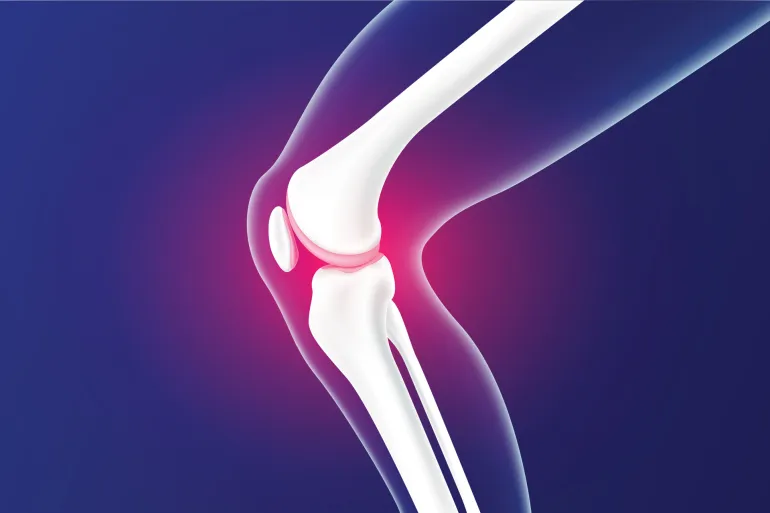

تمارين قوة التحمل تثبت فعاليتها في تخفيف أعراض الفصال العظمي للركبة

أوضح موقع “أبونيت.دي” -البوابة الرسمية للصيادلة الألمان- أن المصابين بالفصال العظمي في مفصل الركبة يعانون عادة من الألم وتقيّد الحركة، إضافة إلى التورم وصدور صوت طحن عند الحركة، مشيرًا إلى أن ممارسة التمارين الرياضية يمكن أن تسهم في الحد من هذه الأعراض بشكل واضح.

ويُعد الفصال العظمي للركبة من الأمراض التنكسية المزمنة الناتجة عن تآكل غضروف المفصل وتلفه مع مرور الوقت، ويتطلب اتباع أساليب علاجية متدرجة تشمل النشاط البدني للحفاظ على الحركة والحد من الألم.